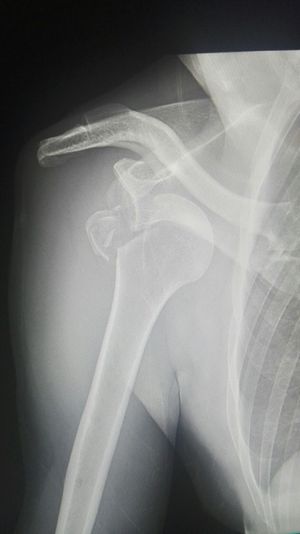

Xray

Fracture

Shoulder

Dislocated